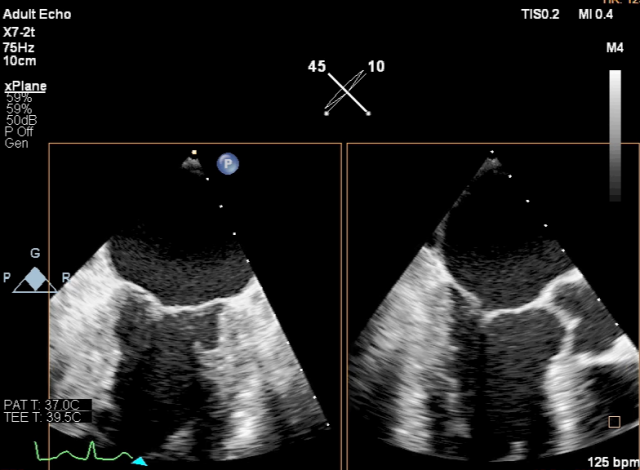

麻醉状态下TEE显示中大量返流MR:

房间隔穿刺:

Bicaval 寻找穿刺点

穿刺点距离二尖瓣环3.42cm